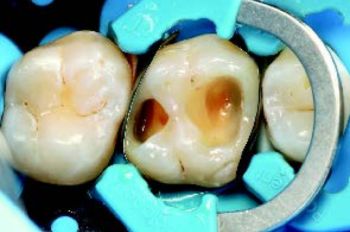

Et seksjonsmatrisesystem konverterte kaviteten til klasse I, noe som ga bedre tilgang og kontroll. Hele kaviteten ble etset med 35 % fosforsyre, deretter behandlet med GC G2-BOND Universal (primer og bond) før lysherding.

Approximalflater ble bygd opp med GC G-ænial A’CHORD A2 (Fig. 3), og dentin ble erstattet med GC everX Flow Dentin for styrke og dybde. Den okklusale emaljen ble lagt inkrementelt med GC G-ænial A’CHORD A2 og modellert med mikrobrush og GC Modeling Liquid.

Figur 3 venstre: Oppbygging av proksimale vegger etter plassering av matrisesystem og bondingprosedyre.